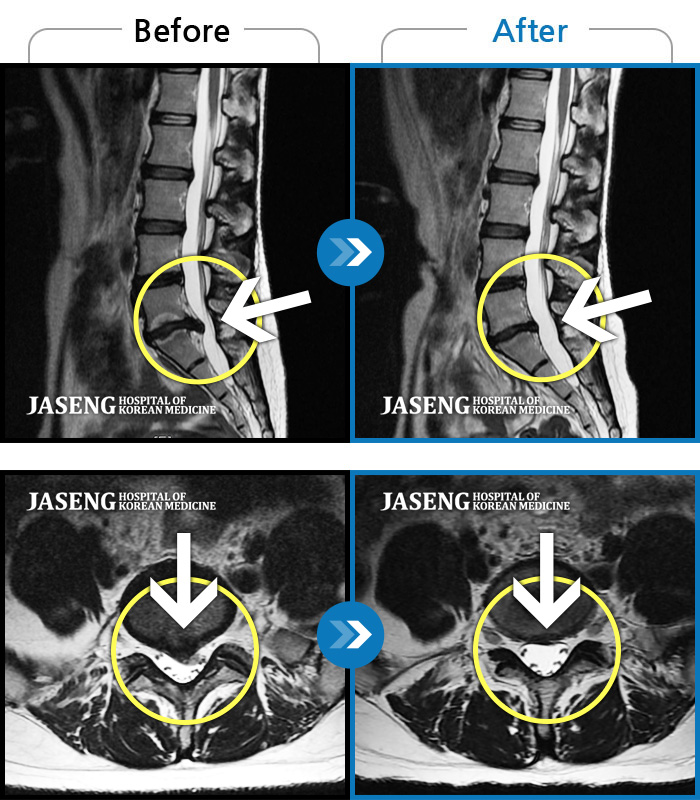

Before

After

앉아 있다가 일어설 때 통증이 증가합니다. 좌측 엉덩이부터 발까지 저립니다.

2023.08.05 ~ 2024.02.28